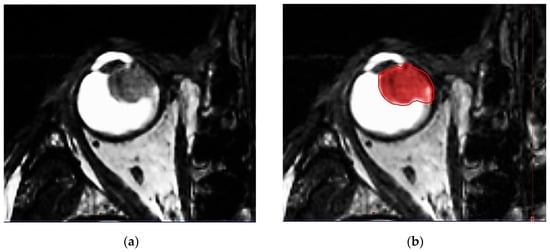

IG-VMAT demands an image guidance-based treatment modality. All relevant anatomic features of the patient (eye bulb, lacrimal gland, lens, optic nerve, retina, sclera, contralateral eye structures, brain, hippocampi, etc.) are defined. High 3D spatial accuracy and tissue contrast definition are important features for using IG-VMAT-SRS to its utmost positional exactness [19,20]. A thin-layer MR was acquired, using 0.6–1.0 mm layers with stable, reproducible view fixation (3T MRI scanner). The pre-therapeutic gross tumor volume (GTV) was preferably delineated, based on a contrast-enhanced, fat-saturated T1 sequence (1 mm multiplanar reformation or reconstruction (MPR), and 1–2 mm turbo spin echo (TSE) DIXON technique) in all MR planes (coronal, sagittal and axial). In addition, thin-slice T2 sequences were performed, to check tumor spread and anatomy (Figure 2a–d).

Figure 2.

(a) Highly prominent choroidal ciliary body melanoma, axial plane, MR T2 ciss sequence, 0.5 mm. (b) Highly prominent choroidal ciliary body melanoma, axial plane, MR T2 ciss sequence, 0.5 mm, definition of the uveal melanoma. (c) Highly prominent choroidal melanoma, axial plane, MR T1 TSE sequence, bilateral retinal detachment. (d) Highly prominent choroidal melanoma, axial plane, MR T1 TSE sequence, bilateral retinal detachment, gross tumor volume (GTV) definition.